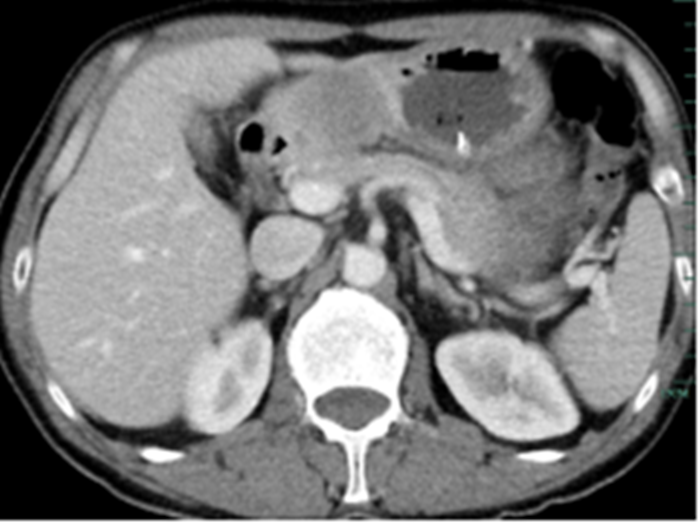

住院后經(jīng)胸腹部CT檢查,提示周先生胃部巨大腫塊穿破胃腔,可能累及到結(jié)腸,同時合并有胃旁淋巴結(jié)轉(zhuǎn)移、肝臟的轉(zhuǎn)移??吹竭@個檢查報告后,周先生和他的愛人一下子就泣不成聲了。

治療前的腹部CT提示胃

經(jīng)過6個周期,前后4個月的治療,周先生再次復(fù)查CT,提示胃部腫瘤,轉(zhuǎn)移的胃旁淋巴結(jié)、肝臟腫瘤都有明顯縮小,營養(yǎng)狀況良好,能正常進(jìn)食,體重增加了6斤,精神狀態(tài)比原先好了很多。

治療前

治療后